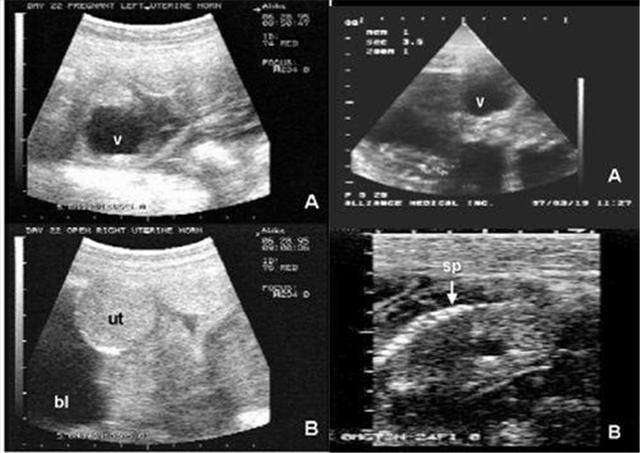

隔了一段时间,小丽总能闻到一股臭臭的味道,不知道是从哪里传来的。找了半天也没有找到这味道是从哪里来的,但是味道又不怎么强烈,而且每次穿的衣服也会有这种味道。在怀孕20周的时候,去医院做产检,医生在经过详细的检查后,给小丽说了一句:“你的宝宝可能是个兔唇”,这可把小丽吓坏了,甚至都要哭了,不知道如何是好!但是医生又说:“这是一种可能,你最好去做个四维彩超确定一下,不过都快要生了,别多想了!”虽然是安慰小丽的,但是小丽知道这意味着什么。马上给老公打电话,叫他陪自己去做个四维彩超,没想到检查结果验证确实有很大可能是兔唇宝宝,但是老公劝小丽,“不要多想了,先把孩子生下来,再说轻微兔唇能够治疗好的”。

生完宝宝后,发现宝宝真的有轻微唇裂,其他的地方都很正常。医生也建议唇裂宝宝一定要等宝宝稍微大点就去做手术,能够恢复过来的,还让我们不用担心。不过看着怀中的唇裂宝宝,真心觉得对不起他,想想都觉得自己好无知!